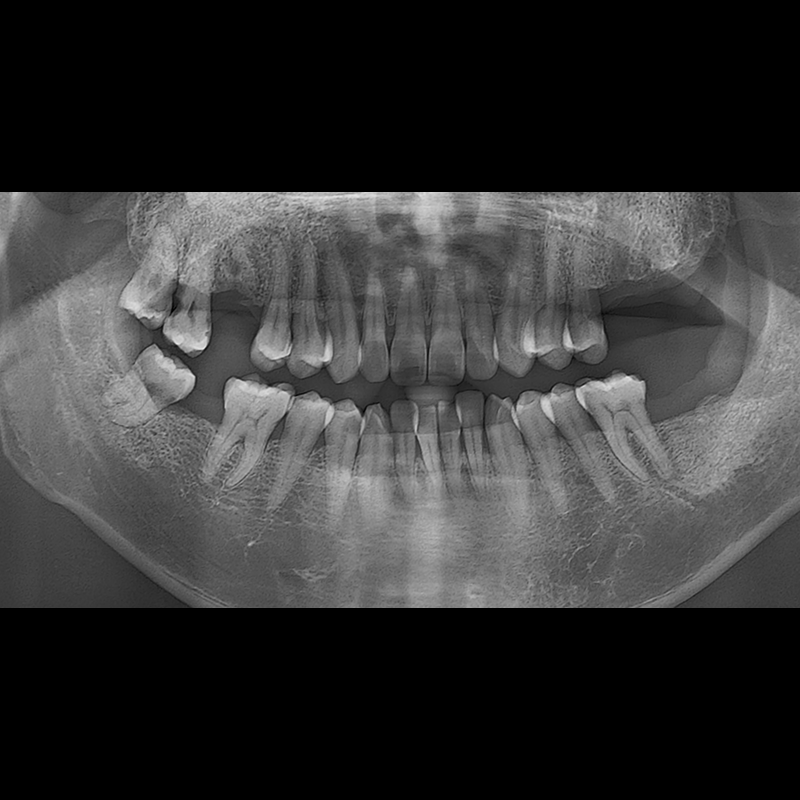

BEFORE AFTER

种植牙前后的照片 2025.05.30

在缺失的牙齿部分和难以挽救的牙齿位置植入了种植牙。